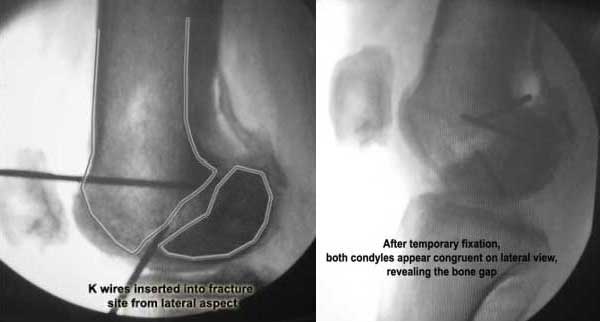

I opened it up from the lateral aspect.

Freed up the non-union site with minimal disturbance to the posterior and lateral soft tissue attachments on the lateral condyle fragment.

Applied a distractor between femoral shaft and tibia, to create a space on the lateral aspect.

This brought the lateral condylar fragment into a position that seemed to be reasonably well aligned, but showed up a bone gap.

This was fixed temporarily, bone grafted with tricortical struts, and fixed by two cancellous screws. The fragment was not large enough to afford any fixation to a plate or such implant, and the screws held it compressed well to the rest of the distal femur.

Post-op - limb is well aligned, rom 0-30, but I am not pushing that right now, for the next two or three weeks.

Further plan - hope that the screws hold the fragment appropriately till union, but if the stability on table is anything to judge by, that should not be a problem.

Quadricepsplasty after a year or so, to restore flexion.

Pictures attached.

Mangal Parihar